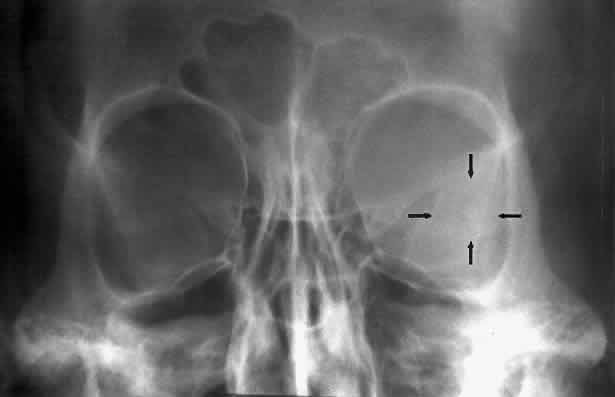

The orbital floor consists of the maxillary, zygomatic, and palatine bones. The floor is thinnest medial to the infraorbital canal, which is the location of most orbital floor fractures (Fig. 7). As mentioned earlier, the floor slopes upward from the lateral to the medial wall. The floor extends toward the orbital apex but does not reach the apex. This orientation of the floor makes frontal projections more informative than the lateral projection.

Fig. 7. A patient involved in a motor vehicle accident who sustained a right orbital floor fracture. Soft tissue density (arrow) located in the roof of the maxillary sinus. Disruption of the orbital floor is seen at the fracture site.

Waters view gives the best image of the anterior and middle portion of the floor. This is possible because extension of the neck brings the floor into a position that is tangential to the x-ray beam. The floor is represented by the most inferior radiopaque line, whereas the orbital rim will be the line above it.10 The vertical distance between these lines should be approximately 1 cm.19 This relationship between the floor and the orbital rim should be symmetric between the two orbits. Any asymmetry should suggest a fracture of the orbital rim or floor.